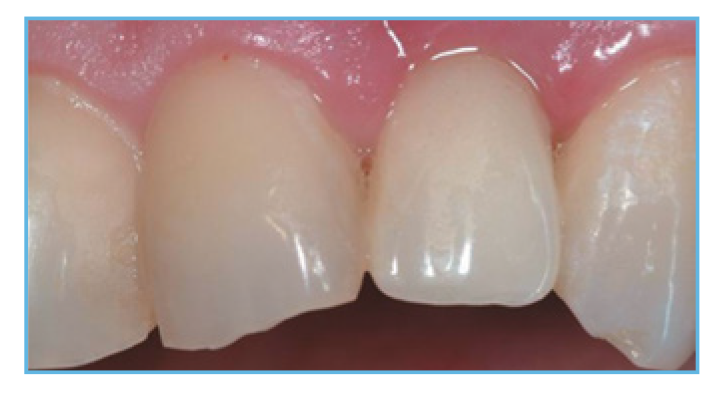

Fig. 5. The provisional restoration was fabricated, occlusal and interproximal contacts were checked, adjusted accordingly, and delivered to the patient.